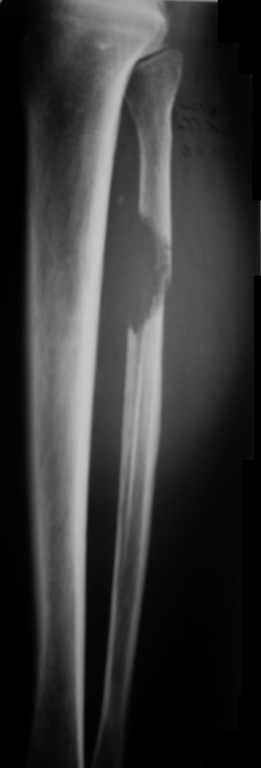

Всем привет!Кому интересно - может лицезреть мое личное наблюдение первичной костной лимфомы с поражением правой большеберцовой кости (см. аттач). Пациент: мужчина, 46 лет. Анамнез прослеживается в течение 1,5 лет - начало заболевания с появления болей.С уважением, Виталий Тазалов.

Ещё одно клиническое наблюдение - лимфома кости, до и после ПХТ и лучевой терапии.

Примите мои извенения, если я Вас чем-либо обидел. Никакого пренебрежения, просто хотел поделиться наблюдением, а главное, результатом консервативного (ПХТ и лучевая терапия) лечения.